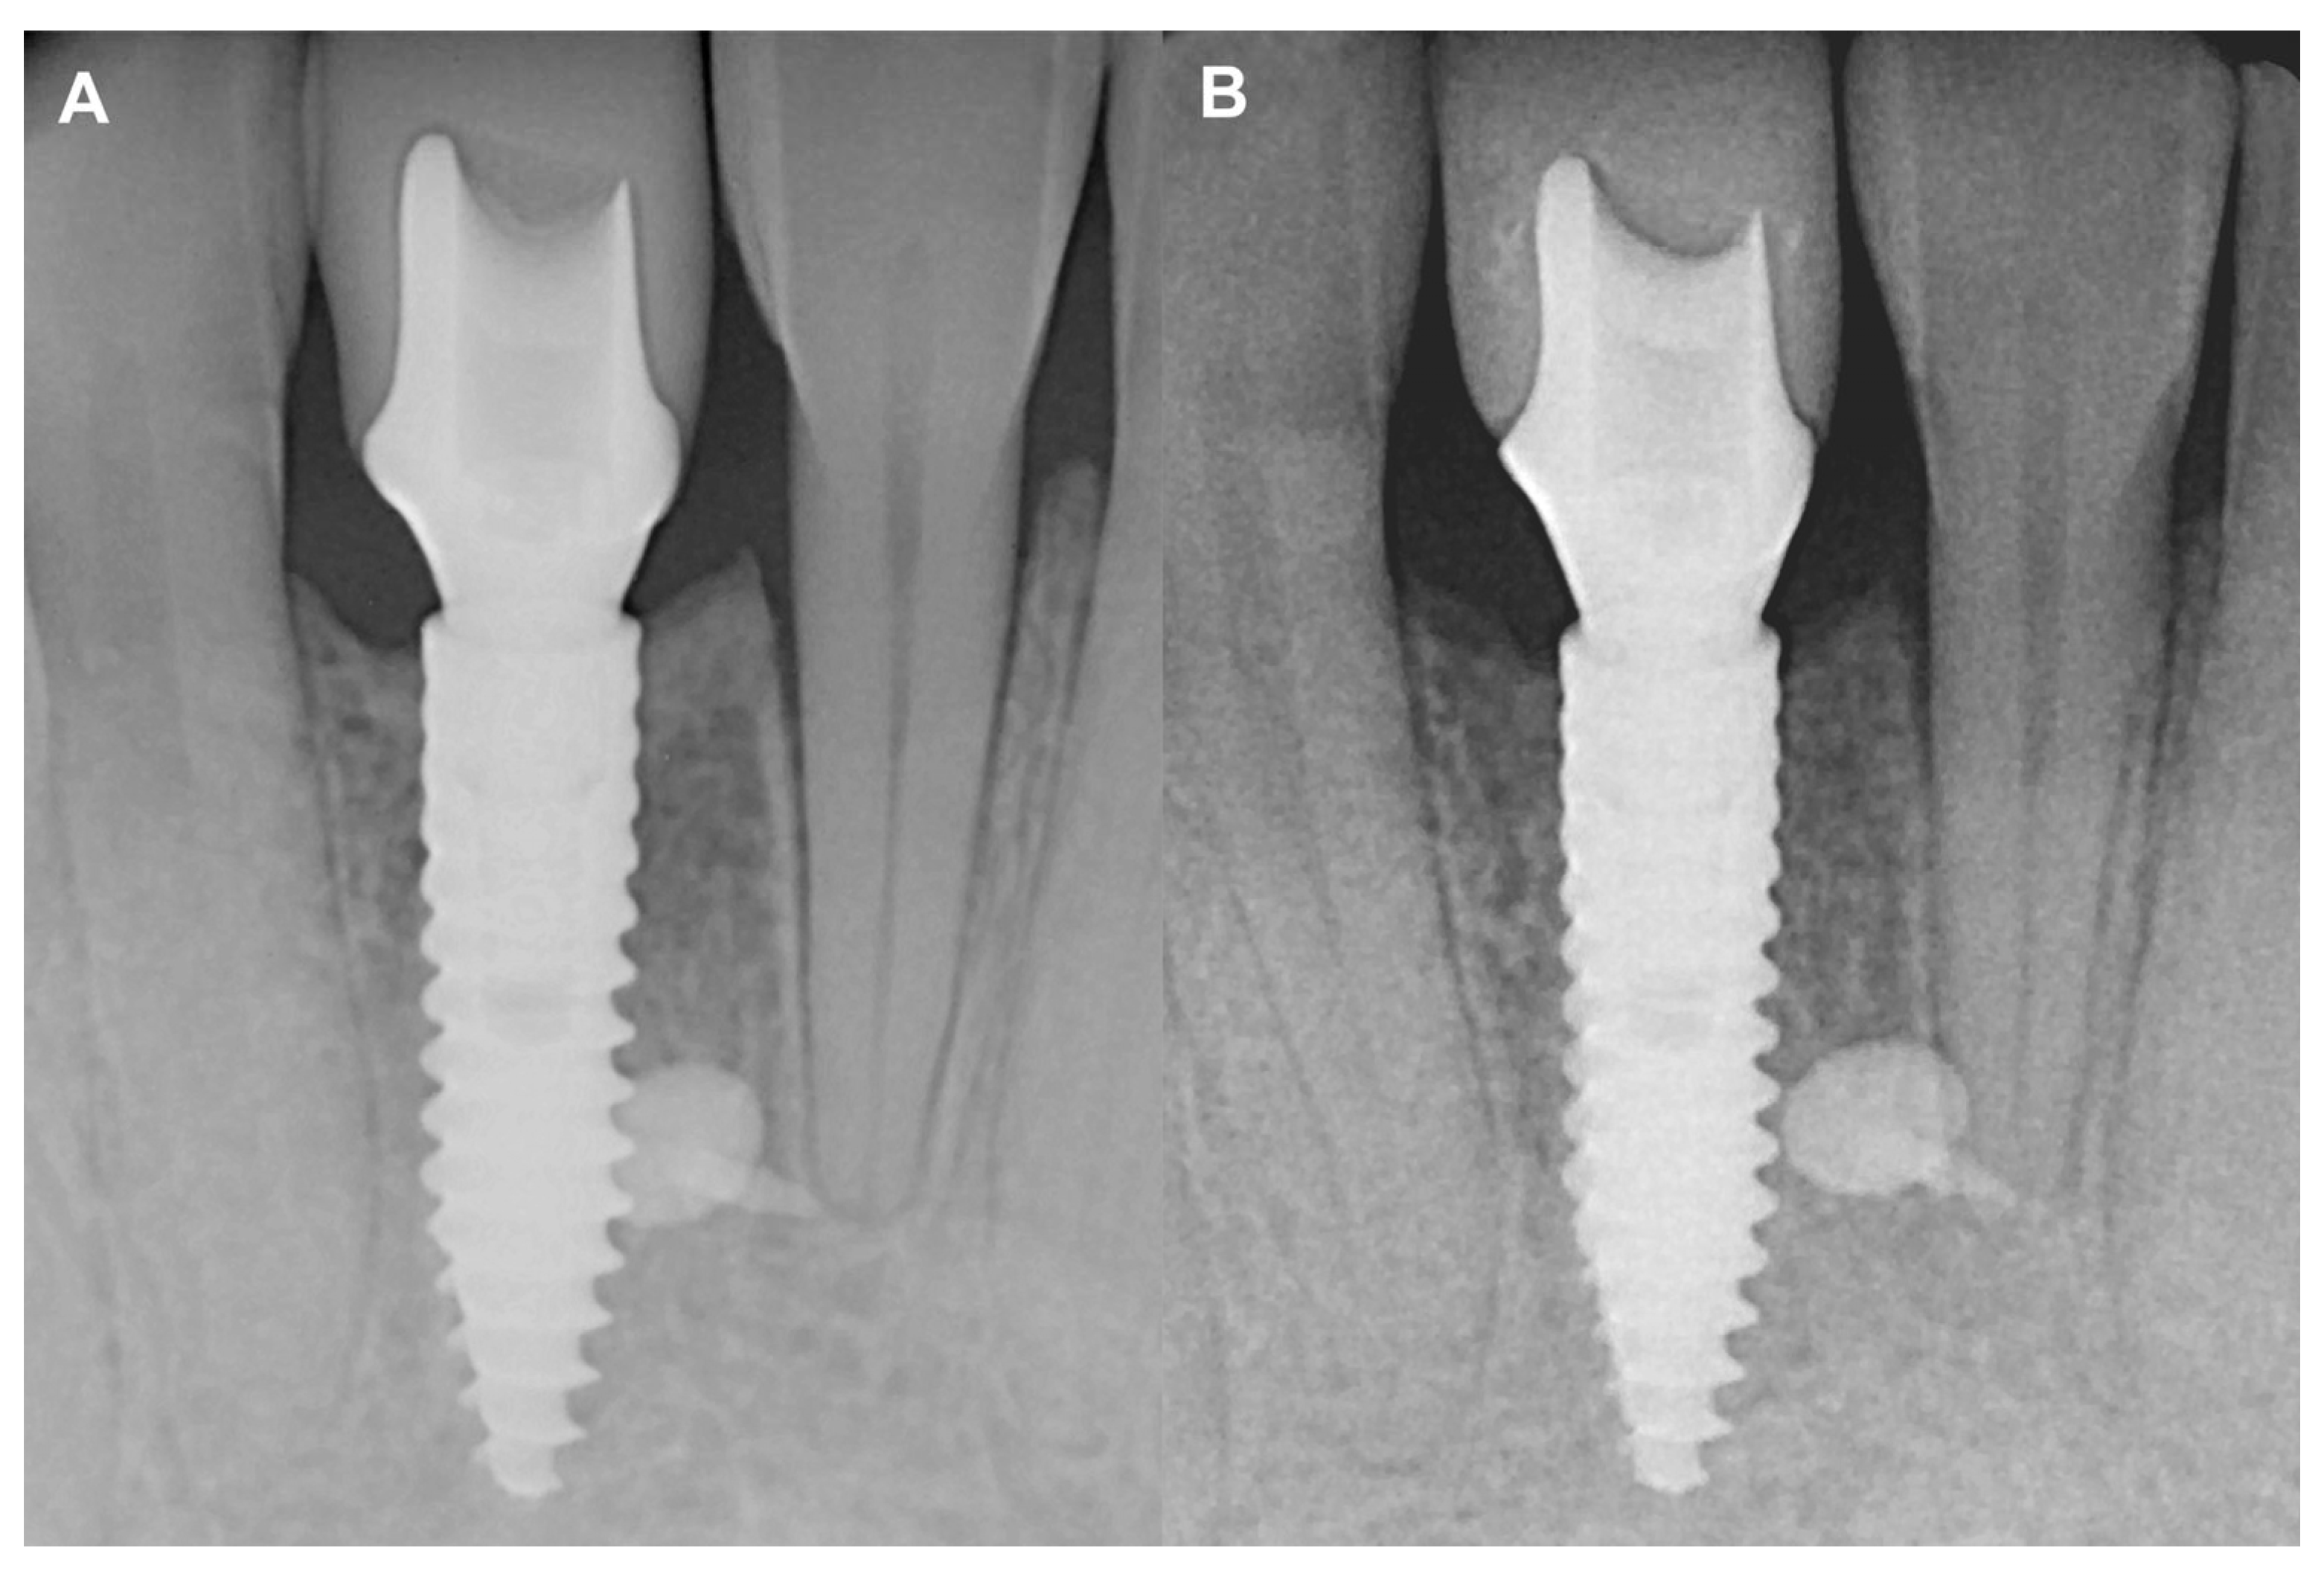

3.1. Case #1

3.1.1. Baseline Clinical Situation

3.1.2. Short-Term Hard Tissue Gain and Two-Year Follow-Up

3.2. Case #2

3.2.1. Baseline Clinical Situation

3.2.2. Short-Term Volumetric Hard Tissue Gain and Long-Term Follow-Up